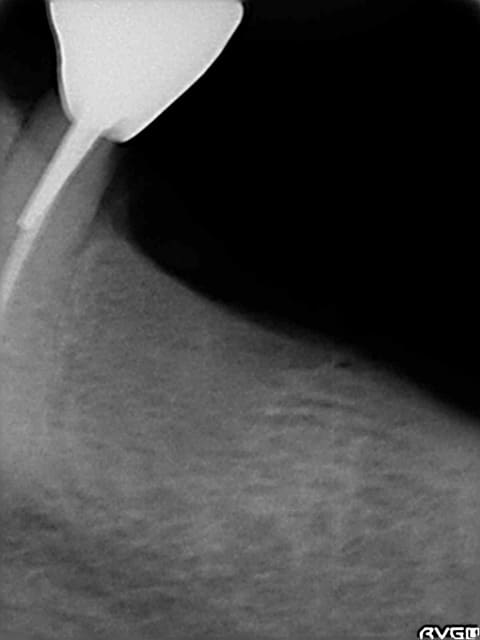

derniere radio faite avec angulateur .... et en mars 2010

la crete est tres large et peu de concavite en L.

c'est juste la longeur qui m'inquiete

le cone apres extr dans l'alveole mesure 19 mm et avec la radio je mesure 18 mm : il y a peu de deformation

dans un tel cas, le scan me permet de juger de la concavité linguale mais aussi de choisir le diamètre d'implant maximum possible.